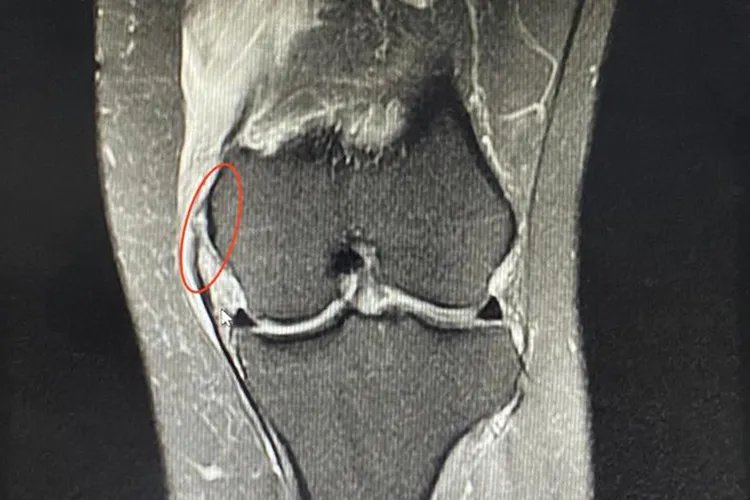

膝盖各个部位疼痛可能与髌骨骨折、内侧副韧带损伤、腘窝囊肿等疾病有关,具体症状如下: